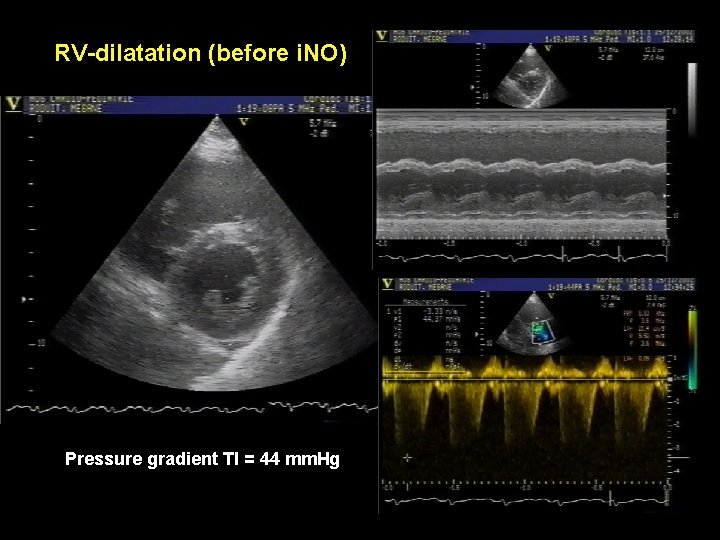

RV-dilatation (before i. NO) Pressure gradient TI = 44 mm. Hg